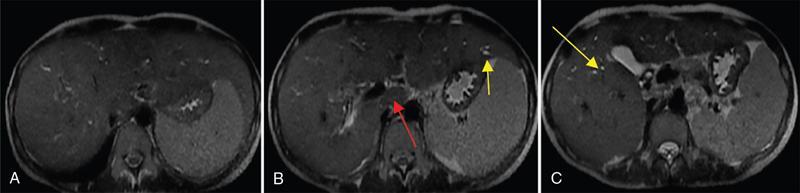

Ritu K. Kashikar, Shrinivas B. Desai, Chandresh Karnavat, Nilesh Doctor The biliary tract is subject to a variety of abnormalities. The spectrum includes benign diseases of autoimmune, infective, ischaemic, infiltrative aetiologies and malignant disorder, which most importantly represents cholangiocarcinoma. Imaging in particular magnetic resonance cholangiopancreatography (MRCP) plays a vital role in diagnosis and follow-up of these disorders. Multidetector computed tomography (MDCT) and magnetic resonance imaging (MRI) are also crucial in preoperative staging of biliary malignancies and making decisions regarding resectability and extent of resection. This chapter focuses on important benign and malignant disorders of the biliary tree and imaging features that aid in differentiation of various entities. A variety of disorders affect the biliary tree. Most biliary disorders manifest as biliary dilatation. The various causes are listed in Table 9.15.1. Imaging plays an important role in identification of aetiology based on pattern of involvement in association with clinical picture. USG is often the first investigation in a patient with jaundice. USG is excellent at showing biliary dilatation. It may be useless in assessing level of obstruction and biliary stones. Changes in liver morphology, development of cirrhosis is accurately done on USG. Early changes in conditions like primary sclerosing cholangitis (PSC), presence of intrahepatic ductal strictures, thickening of common bile duct (CBD) are, however, not confidently seen and need imaging modalities like MRCP and computed tomography (CT). Staging of hilar cancers is also best done on CT or MRI with contrast. Contrast-enhanced CT is extremely accurate in staging hilar cancers. It is a preferred modality to access radial spread of the disease and vascular involvement. Subtle changes of PSC and autoimmune cholangitis may however be missed and MRCP is preferred in these conditions. The protocol for evaluating biliary disease is standard plain scan followed by early, late arterial, portal venous and parenchymal phases similar to that obtained for focal liver lesions. Delayed phase images should be obtained for hilar malignancies, which often show delayed enhancement. MRCP with or without contrast is the modality of choice in diagnosing and characterizing biliary diseases. Owing to its noninvasive nature, it has replaced endoscopic retrograde cholangiopancreatography (ERCP) in the initial evaluation and follow-up of a variety of biliary pathologies. Absence of radiation exposure makes it suitable to obtain follow-ups in patients requiring serial scanning. The ability to diagnose abnormalities of both intra- and extrahepatic biliary tree, level of obstruction, longitudinal and radial spread of neoplastic process make it an ideal modality. MRCP protocol includes T2 weighted single-shot fast spin-echo, T1 weighted in phase and opposed phase gradient echo, diffusion-weighted imaging, T2-weighted fat-suppressed fast spin-echo in axial and coronal. A pre contrast three-dimensional T1-weighted fat-suppressed spoiled gradient-echo image is obtained in addition to 3-D MRCP. Postcontrast protocol includes dynamic three-dimensional T1-weighted fat-suppressed spoiled gradient-echo (in arterial, late arterial and portal venous, parenchymal and delayed phases). Since the advent and widespread use of MRCP, the utility of ERCP in diagnosing biliary pathologies has significantly reduced. ERCP is primarily used when stenting or other procedures need to be performed in the same setting. Although an invasive procedure with postprocedural risk of pancreatitis ERCP allows excellent depiction of biliary changes in conditions like PSC, recurrent pyogenic cholangitis (RPC) and IgG4-related disorders. Endoscopic USG (EUS) is an excellent modality in diagnosing lower bile duct pathologies and also has the added advantage of obtaining a biopsy in the same setting. EUS is less invasive than ERCP and overall safer. PSC is a premalignant cholestatic liver disorder characterized by bile duct strictures secondary to bile duct inflammation and fibrosis. Cirrhosis of liver can develop secondary to this condition and patients are at a high risk for biliary and colonic cancers. PSC is a relatively rare disease, with an incidence of less than 50 per 100,000 patients though it varies in various location. It is diagnosed in young patients aged 30–40 years and is twice as common in men than in women. Similar to other autoimmune diseases, genetic susceptibility is likely to be instrumental in the development of PSC after exposure to a trigger. There is also a strong association between PSC and human leukocyte antigens (HLAs). Environmental factors such as childhood microbial exposure also play an important role in disease pathogenesis. A strong association of PSC with inflammatory bowel disease (IBD) is seen. There is a 100-fold increased risk of developing PSC among siblings. PSC can be asymptomatic but may present with cholestatic symptoms such as jaundice, pruritus, fatigue and right upper quadrant pain, steatorrhoea and episodes of acute bacterial cholangitis. There is marked elevation of alkaline phosphatase (ALP). A twofold to threefold increase in serum alanine and aspartate aminotransferase (AST) can be seen. Elevated bilirubin is usually seen in advanced disease, malignancy or those with choledocholithiasis. Various serum antibodies can also be elevated in PSC. These have been enlisted in Table 9.15.2. On liver biopsy, classic pathologic features of periductal concentric fibrosis or ‘onion skin’, around the affected ducts can be seen. This is however not a pathognomonic finding and is seen in less than 40% of biopsy specimens. Therefore, biopsy is not routinely used as a diagnostic tool for PSC and is reserved primarily for disease staging. MRI with MRCP best depicts the biliary changes in PSC and is the modality of choice. While CT and USG may show biliary dilatation and changes of cirrhosis in advanced cases, they fail to show early changes (Table 9.15.3). USG is an effective modality for the visualization of dilatation and diffuse wall thickening of the extrahepatic bile duct. Other feature seen on USG is bright echogenic portal triad. However, the role of USG in the diagnosis of early PSC is limited owing to suboptimal assessment of the intrahepatic biliary ducts. Features of advanced disease such as heterogeneous coarse echogenicity can be readily detected with USG. The major benefit of performing US is to guide liver biopsy. Also, liver stiffness as assessed by transient elastography correlated well with the degree of liver fibrosis in PSC patients. CT can demonstrate some findings suggestive of sclerosing cholangitis such as focal, discontinuous, often peripheral intrahepatic biliary duct dilatation and thickening with enhancement of the bile ducts owing to inflammation. CT is effective in helping exclude other causes that can result in biliary stasis and dilatation such as hepatic and pancreatic lesions. CT is also excellent in diagnosing tumours, which may sometimes have similar presentation. Concomitant changes of IBD, if present, can be seen. However, CT is limited in assessment of biliary strictures and visualization of disease involving small peripheral bile duct, especially in the early stages of the disease. CT shows changes of cirrhosis in liver and assessing changes of portal hypertension. MRCP is diagnostic imaging modality of choice in the workup of patients with suspected PSC, as recommended by both the AASLD and EASL guidelines. MRCP has high diagnostic sensitivity (86%) and specificity (94%) for the detection of PSC (Table 9.15.3). Multifocal short segmental strictures in the intra- or extrahepatic biliary tree with intervening normal or dilated duct leading to beaded appearance are seen in early disease. The location in strictures is usually at the biliary bifurcation and are disproportionate to upstream dilatation. Advanced cases show pruning of peripheral biliary radicals secondary to advancing fibrosis obliterating the smaller ducts. An obtuse angle between the central and peripheral ducts is suggestive of PSC. Diverticula and webs also can be seen, though not pathognomonic (Table 9.15.4) (Figs. 9.15.1–9.15.3). Strictures of the CBD of less than 1.5 mm and of left, right or common hepatic duct (CHD) of less than 1 mm are defined as dominant stricture. A dominant stricture is associated with worse prognosis in part due to development of cholangiocarcinoma. MRCP plays an important role in raising the suspicion and guiding treatment. A dominant stricture may be confused with hilar cholangiocarcinoma on imaging and it is often impossible to distinguish the two based on imaging alone (Table 9.15.4) (Fig. 9.15.4). Changes in liver morphology are seen in the form of distortion. The classical change described in PSC includes hypertrophy of the caudate lobe and atrophy of the left lateral and right posterior segments of the liver. Hypertrophy of caudate lobe is more frequent in PSC than cirrhosis from other aetiologies. Other parenchymal changes include heterogeneity of liver, periportal cuffing, peripheral inflammation, cirrhosis and features of portal hypertension. Hyperintensity of the liver parenchyma in PSC on nonenhanced T1-weighted images has been reported. Wedge-shaped peripheral atrophic areas of confluent hepatic fibrosis are seen as high T2-weighted signal intensity. Periportal oedema is visualized as high signal intensity in periportal region on T2-weighted. Increased heterogeneous peripheral enhancement of the liver parenchyma can be seen and is likely due to the altered blood supply in those areas in response to parenchymal inflammation (Table 9.15.4) (Figs. 9.15.5 and 9.15.6). MR elastography is the most accurate noninvasive method for the diagnosis and staging of liver fibrosis and could potentially replace liver biopsy. It is predictive of progression to decompensated liver disease. However, lack of wide availability are still major limiting factors. MR elastography is not influenced by obesity or anatomical conditions (e.g. narrow intercostal spaces and ascites) and the sample size of the liver is significantly higher and hence has several advantages over ultrasound elastography (Table 9.15.5). Besides these features, enlarged reactive abdominal lymph nodes, commonly periportal and portocaval lymph nodes, are commonly diagnosed in PSC and should not be misdiagnosed as a lymphoproliferative disorder or metastatic disease. Though ERCP has higher diagnostic accuracy in detecting PSC, its role is limited to intervention required in PSC due to its invasive nature and potential complications. Also it is recommended that MRCP be performed prior to ERCP as a preprocedural MRCP can provide a road map to the endoscopist. Small duct PSC is a variant PSC syndrome with biochemical markers and histologic features suggestive of PSC with normal cholangiography. It is associated with better prognosis. Approximately one-fourth of patients’ progress to classic PSC in an average of 8 years. Bile duct calculi are a common complication of PSC. Pigmented bile duct stones are common owing to biliary stasis. Both intrahepatic and extrahepatic biliary stones can be found. However, the presence of biliary tree stones is not an essential diagnostic feature. Soft calcific foci within dilated bile ducts can be seen on US and CT images. MRI with MRCP is the imaging modality of choice to detect bile duct stones and appear as focal areas of signal-intensity-void filling defects on T2-weighted images. Usually isointense at T1-weighted imaging but frequently are hyperintense. The presence of biliary strictures puts these patients at risk of bacterial cholangitis in PSC patients. The classic Charcot triad of fever, abdominal pain and jaundice can be seen. Early enhancement of the biliary wall due to the biliary duct inflammation is a common finding with peribiliary reactive hepatic parenchymal changes. Cholangitic abscesses may sometimes be seen. PSC patients are at high risk of developing cholangiocarcinoma during the disease course with and a total risk of 10%–15%. Approximately 30% of all cholangiocarcinomas are detected within the first year of establishing a diagnosis of PSC and so it is important to be suspicious even at the time of PSC diagnosis and to survey for early detection. Rapid clinical deterioration, worsening of jaundice, pruritus, weight loss along with elevation in serum bilirubin and ALP should raise suspicion of PSC. It may be difficult to distinguish benign from malignant strictures. Progressive bile duct wall thickening, irregularity, enhancement, new onset biliary dilatation, dominant stricture or development of focal strictures with dilatation and ipsilateral atrophy are indeterminate features that may raise possibility if occult cholangiocarcinomas. Perivascular thickening, vascular involvement or occlusion are features favouring malignancy. Definite diagnosis is however often not possible on imaging alone and a brush biopsy should be taken in patients with new onset clinical symptoms, elevated tumour makers or above-mentioned indeterminate imaging features (Table 9.15.7). The most common subtype of cholangiocarcinoma in PSC patients is periductal type, characterized by long segment irregular wall thickening along the bile duct with no identifiable mass. The lesion is hypointense on T1W1 images and hyperintense on T2W1 images showing progressive enhancement on contrast study. The tumour could be at the bifurcation and can cause abrupt cut-off, commonly presenting as Klatskin tumour (Fig. 9.15.7). Combined UC and PSC is associated with a higher risk for colorectal carcinoma than UC alone. PSC is considered as an independent risk factor for development of colorectal carcinoma in patients with UC. Malignancy tends to involve the right colon or more proximal parts of the colon. Clinical presentation and history in patients with ascending cholangitis differ from those with PSC. Fever, pain and jaundice dominate the presentation in patients with ascending cholangitis while patients with PSC may be asymptomatic. The typical findings of PSC including biliary duct stenosis, beading or pruning are not typical findings in the newly diagnosed cases of acute ascending cholangitis. Wedge-shaped peripheral and/or intrahepatic peribiliary foci of increased T2 signal around the dilated radicals with arterial and/or delayed parenchymal enhancement has been described in ascending cholangitis. Patients with RPC present with recurrent episodes of abdominal pain, fever, jaundice and chills. These features differ from those in patients with PSC. Hepatolithiasis with pigmented stones in the biliary tree and upstream and downstream duct dilatation are typical imaging features in RPC (Table 9.15.8). Ischaemic cholangiopathy is a form of biliary injury resulting from decreased arterial supply. History of liver transplantation is the key in diagnosing ischaemic cholangiopathy. Biliary strictures in AIDS cholangiopathy are indistinguishable from PSC. However, the combination of papillary stenosis and intrahepatic ductal strictures appears relatively unique to AIDS cholangiopathy; this combination is not found in PSC. Clinical history may help to distinguish one from the other. Effective medical therapy for PSC is lacking. Oral ursodiol (ursodeoxycholic acid) is one of the main treatment options of cholestatic diseases though does not prevent disease progression. Azathioprine and steroids are recommended for use in patients with AIH as well as those with AIH–PSC overlap syndrome. Vedolizumab is a gut-specific monoclonal antibody that has been tried but the clinical utility in PSC–IBD patients remains under investigation. Dilatation of biliary strictures, stenting, lithotripsy and stone extraction can be done with the aid of ERCP and percutaneous transhepatic cholangiography (PTC). The only definitive cure of PSC is, however, liver transplantation. Treatment of complications like choledocholithiasis stone removal can be accomplished by using standard endoscopic techniques with or without sphincterotomy, with balloon or basket extraction for extrahepatic biliary stones. For bacterial cholangitis, immediate administration of broad-spectrum antibiotic therapy is recommended and in abscess formation percutaneous drainage with intravenous antibiotic therapy shows favourable outcome compared with surgical drainage. Incidence is 20%–25%. Diagnosis of recurrent PSC requires careful evaluation, as there are other causes of biliary changes after liver transplant with similar features. Nonanastomotic biliary strictures imply the diagnosis of recurrent PSC only if they occur more than 90 days after transplant. Characteristic multifocal strictures and segmental dilatations of biliary ducts are suggestive findings. MRCP is the initial modality. RPC is characterized by a triad of recurrent biliary sepsis, inflammatory biliary strictures and intrahepatic stones. Fifty per cent of patients may have acute pancreatitis. Oriental cholangiohepatitis, primary hepatolithiasis, Hong Kong disease and oriental infestational cholangitis. Prevalence in the third and fourth decades of life with equal frequency among men and women peak. Southeast Asia predominantly in rural population and in lower socioeconomic groups. Gut-derived organisms lead to sepsis, which initiates a cascade of events, which leads to a chronic, progressive and recurrent inflammatory process in cholangioles. Associations with Clonorchis sinensis, Opisthorchis species, Fasciola hepatica and Ascaris lumbricoides infestations have been suggested. Common organisms cultured from bile include Escherichia coli, Klebsiella, Pseudomonas and Proteus species and anaerobes. Structural biliary abnormalities may develop before stones are demonstrable. Strictures may be seen at cholangiography without stones and vice versa. Entrapped stones cause stasis, sepsis, scarring and stricturing with the increasing lithogenicity (Table 9.15.9). Typically present with abdominal pain, fever and jaundice (the Charcot triad) and commonly provide history of repeated episodes. Routine investigations may demonstrate leukocytosis, deranged liver enzymes with obstructive pattern. Elevated cholestatic markers (bilirubin, ALP and gamma GT) and deranged LFTs can be seen. Serum inflammatory markers can be elevated. Additional tests aiding in differential diagnosis include autoantibodies, ANCA, CA19-9 and serologic tests for Echinococcus. Histology is usually not required. It shows fibrous mural thickening of bile ducts and periductal tissue, as well as acute and chronic inflammatory changes. The imaging features include changes in bile ducts, development of calculi and changes in the parenchyma. The disease affects intrahepatic ducts more than the CHD and CBD. Disproportional dilatation of central intrahepatic ducts and extrahepatic bile ducts is seen with nondilated or minimally dilated peripheral ducts, leading to abrupt tapering of bile ducts. All segments of biliary tree may be involved, but the lateral segment of the left lobe is most often and extensively involved most likely because left hepatic ducts come off at a more acute angle compared with the right hepatic ducts, thus predisposing to stasis and stricture formation (Table 9.15.10). Hepatolithiasis is common in patients with RPC. Stones are composed mainly of bile pigments with variable calcification. There may be single or multiple stones scattered in the intra- or extrahepatic ducts or both. The dilatation of the extrahepatic duct is generally not related to the location of the stone. Ducts both proximal and distal to the stone are dilated. Parenchymal atrophy most commonly involves the left lateral and right posterior segments while hypertrophy of the caudate and right lobe is seen. USG shows dilatation of the central intrahepatic and extrahepatic ducts, with relative sparing of the peripheral biliary tree. Hepatolithiasis can be seen in 90% of cases. The echogenicity and acoustic shadowing of calculi may vary depending on extent of calcification. There is often associated periportal echogenicity. Ultrasound may be useful in performing image-guided percutaneous drainage of abscesses or biopsy of suspicious lesions. Limitations include inability to detect subtle intrahepatic ductal dilatation and heavy stone burden obscuring evaluation of underlying hepatic parenchyma. Contrast-enhanced CT is increasingly being used as first line of imaging. It allows for detection of characteristic disproportionate dilatation of the extrahepatic and central intrahepatic ducts. Contrast-enhanced CT also allows for detection of bile duct wall enhancement, suggestive of acute cholangitis. Ninety per cent stones are hyperdense to liver parenchyma on nonenhanced scan. Extent of calcification in calculi may vary. Parenchymal atrophy affects left lateral segment most frequently, followed by right posterior segments. Eventually, changes of cirrhosis can be seen. Heterogeneous appearance of liver parenchyma with segmental steatosis and altered enhancement can be seen particularly during acute attack. Pneumobilia is not infrequent and can usually be attributed to recent procedures or surgeries like bilioenteric anastomosis. It may, however, be seen in patients without history of prior interventions due to recent passage of stone through the ampulla or less commonly cholangitis related to gas forming organisms (Fig. 9.15.8). Subtle intrahepatic ductal strictures and noncalcified stones may be missed on CT. MRCP allows visualization of both intra- and extraductal disease and can reveal complete extent, severity and complications of the disease. Even noncalcified calculi which may be missed on CT or sonography, are seen as intraductal filling defects on heavily T2-weighted images and may appear hyperintense to the liver on T1-weighted images. MRI demonstrates central and extrahepatic duct dilatation with decreased arborization and abrupt tapering of peripheral ducts. MRI particularly MRCP sequences accurately depicts stenotic segments and delineates the entire biliary tree, including the proximal part of the stricture, without risk of aggravating biliary sepsis. Even short segment duct strictures <1 cm are easily seen on MRCP (Figs. 9.15.8 and 9.15.9). Parenchymal abnormalities like hepatic atrophy, whether diffuse or segmental, and altered signal can be accurately diagnosed. Mass lesions and hepatic abscesses, if present, are also well delineated. The characteristic finding of disproportionate dilatation of the ducts, with multiple intraductal calculi are well demonstrated. There may also be intrahepatic strictures, with abrupt tapering of the peripheral ducts as well as decreased arborization of the biliary tree (arrowhead appearance). It allows for better spatial resolution, thus permitting better evaluation of the smaller peripheral ducts. The main limitation of ERCP is its invasive nature, with complications such as ERCP-associated pancreatitis. Heterogeneous parenchymal enhancement, wall thickening and periductal enhancement are seen in acute cholangitis. Abscess formation is encountered in up to 20% of RPC patients who undergo cross-sectional imaging. The abscesses can occur in both the affected and unaffected portions of the liver but most commonly seen in the right lobe. Sonography guided aspiration can be done when diagnosis is doubtful. Intrahepatic bile lakes are not infrequent and may or may not communicate with the biliary tree. On USG bilomas appear anechoic and are usually hypodense on CT with or without calculi. Leakage of bile from a severely dilated obstructed duct may lead to formation of extrahepatic biloma. Cholangiocarcinoma is the most feared complication and may be seen in up to 5% of patients. Segments with high stone burden or those with atrophy are more prone to developing cholangiocarcinoma. Clinical and laboratory indicators for development of cholangiocarcinoma in patients with PSC include increase in jaundice without associated cholangitis, sudden weight loss, significant elevation of ALP and rising tumour markers. Peripheral cholangiocarcinoma manifests as expansion of the affected segment. Hypoattenuating mass with showing peripheral enhancement causing narrowing of the portal vein may raise suspicion of malignancy. Portal vein thrombosis has also been reported but is rare. Recurrent biliary sepsis may lead to periductal inflammation and portal thrombophlebitis. Portal thrombosis can lead to lobar atrophy with compensatory hypertrophy of the uninvolved lobe. Higher incidence of hepatocellular carcinoma (HCC) is reported in patients with RPC due to development of cirrhosis in severe cases. Management should comprise antibiotic treatment, clearance of stones, maintenance of biliary drainage and long-term follow-ups. ERCP allows for therapeutic procedures such as stone removal and stenting of strictures. Destroyed liver segments, those with multiple abscesses and patients with secondary cholangiocarcinoma are candidates or surgery. Stone extraction can also be done surgically with the aid of basket, forceps, balloon catheter or flexible choledochoscope. Transduodenal sphincteroplasty and hepaticojejunostomy are commonly performed drainage procedures. Indications for transplantation include extensive bilobar hepatolithiasis, cirrhosis and liver failure. IgG4 cholangiopathy is a cholangitis characterized by elevated serum IgG4 and infiltration of the bile duct wall with IgG4 positive plasma cells leading to storiform fibrosis and obliterative phlebitis with resultant bile duct wall thickening. This condition shows good response to steroids. Frequent association with IgG4-related autoimmune pancreatitis is seen. IgG4 sclerosing cholangitis (IgG4-SC) has a threefold to fivefold higher prevalence in men than women. It usually presents in the fifth and sixth decades of life. Incidence of this disease is approximated to be around 0.28–1.08/100,000. Autoimmunity has been considered as the most probable pathogenesis of IgG4-related disease (IgG4-RD). Several HLA association have identified as determinants of disease susceptibility. The major histologic features associated with IgG4-RD have been well described and include the steps. Chronic or recurrent cholangitis is the most common presentation and seen in up to 75% cases. Other symptoms seen are fever, pruritus, pain and weight loss. Biliary involvement may be detected incidentally in patients being scanned for symptoms related to involvement of other organs such as pancreas. One-quarter of patients with IgG4-SC may be asymptomatic. Serum liver tests show a cholestatic pattern with often marked elevation of ALP and γ-GT and only mildly increased ALT and AST. Serum bilirubin may be increased. Tumour marker CA 19-9 is not able to distinguish pancreatobiliary malignancies from IgG4-SC since levels of >1000 IU/mL (ULN = 37 IU/mL) may be observed in IgG4-SC. IgG4 levels are elevated (>140 mg/dL) in up to 75%–80% of affected patients. A cut-off level of 207 mg/dL might be useful for completely distinguishing IgG4-SC from cholangiocarcinoma. Elevated bile fluid IgG4 has a high sensitivity and specificity of 100% at a cut-off level of 113 mg/dL and seen only in cases of IgG4-RD, neither PSC nor cholangiocarcinoma. Approximately 40% of patients have peripheral blood eosinophilia, often accompanied by asthma and atopy. Patients may show hypergammaglobulinemia, elevated serum IgE. Several diagnostic criteria have been developed to aid in the diagnosis of IgG4-SC. The most widely used is the HISORt (Histology, Imaging, Serology, other Organ involvement and Response to therapy) criteria of the Mayo Clinic. This tool was initially used to diagnose AIP but can be adapted to diagnose IgG4-SC by Ghazele et al. (Tables 9.15.13 and 9.15.14). It is often the initial investigation and may be normal early in the course of the disease. Circumferential thickening of the bile ducts with biliary dilatation is seen later in the disease. US also helps in the identification of associated findings affecting other organs. However, US has low sensitivity in detecting the disease and is suboptimal for assessing the extent of the disease. Contrast-enhanced CT though not the investigation of choice shows bile duct wall thickening with proximal mild dilatation. The intrapancreatic bile duct segment is more commonly involved. The most important finding is circumferential symmetric wall thickening of the bile ducts, frequently involving the extrahepatic segments, with smooth outer and inner margins. In addition, the thickened segment shows progressive homogeneous contrast enhancement, further increasing in the delayed phase. As opposed to malignancies, wall thickening or stricturing of bile ducts in IgG4-RD is not associated with proportionate proximal biliary dilatation (Figs. 9.15.10 and 9.15.11). In addition to the above findings, imaging findings of IgG4 disease affecting other organs, that is, gallbladder wall thickening, changes of autoimmune pancreatitis, retroperitoneal fibrosis and kidney findings can be seen. MRI is the investigation of choice. MRI findings are similar to CT findings and include circular and symmetric long segmental thickening of the bile duct wall with smooth outer and inner margins. Bile duct wall thickening can be seen in nonstenotic areas as well The other findings are the visibility of patent bile duct in the strictures, disproportionate proximal dilatation, hyperenhancement during the late arterial phase, homogeneous hyperenhancement during the delayed phase, concurrent gallbladder wall thickening and no vascular invasion (Table 9.15.15).